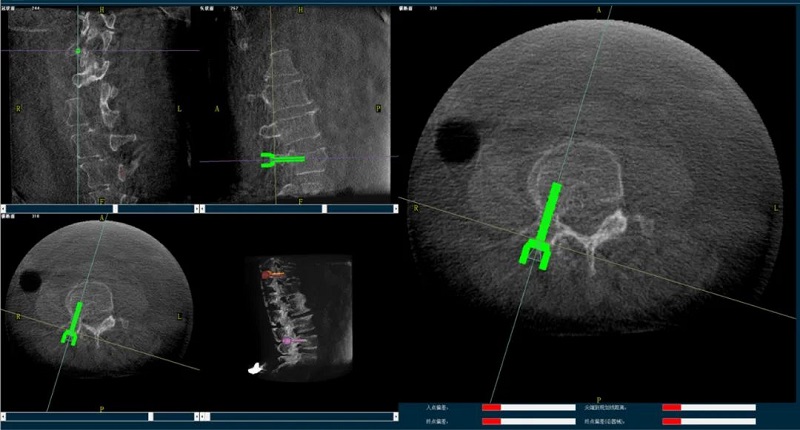

手術機器人規劃圖像

今年3月份,南京醫科大學第二附屬醫院的一名腰椎體壓縮性骨折患者,在接受普愛醫療骨科手術機器人引導完成手術之后,第二天在醫護的指導下即可進行自主翻身,并在腰圍的保護下提早下地活動,疼痛程度明顯減輕,活動較術前明顯改善。

普愛骨科機器人輔助下的骨科手術